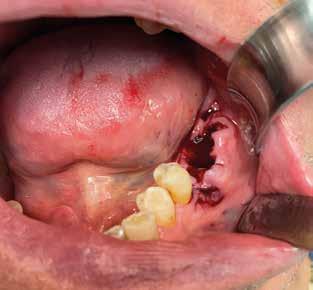

Alla visita di rivalutazione è emerso un ulteriore peggioramento della situazione, confermata anche dall’esame radiografico, con parodontopatia, sanguinamento al sondaggio, infiammazione diffusa, alitosi, difetto parodontale verticale mesiale a 2.3, residui radicolari 1.4, 1.6, 1.7, 3.6, 3.8 e carie destruenti di 1.5, 2.6, 3.5, 3.7 (con lesione endoperio) e 4.7 con estrusione e carie (Figg. 1, 2)

Si è consigliato di procedere per gradi, con bonifica di tutti gli elementi malati e irrecuperabili e successivamente sostituire gli elementi mancanti o con protesi rimovibili o con una protesi fissa sostenuta da impianti (Fig. 3).

La proposta che il paziente ha accettato è stata poi quella, previa bonifica di tutti gli elementi irrecuperabili, di riabilitare con impianti prima il 1° e 4° quadrante e in seguito il 2° e 3° e procedere poi alla protesi definitiva in un’unica soluzione.

riferico. Si è eseguito la maggior parte delle estrazioni in un’unica seduta operatoria, a esclusione degli elementi 2.6 e 4.7 che sono stati mantenuti perché presentavano mobilità ma non segni di focolai infettivi attivi e che si è deciso di estrarre in un secondo momento. Il follow-up post estrattivo ha consentito anche di valutare la risposta tissutale e la guarigione degli alveoli. Non è stata sospesa la terapia con l’acido acetilsalicilico. Il PRGF è stato importante per evitare alveoliti che avrebbero rallentato la guarigione (Figg. 4-6).

L’esame CBCT ha rivelato un quantitativo di osseo sufficiente a procedere con l’intervento implantare, anche se erano ancora visibili le zone delle estrazioni; inoltre ha evidenziato una lesione osteolitica a carico del 3.5 che abbiamo dunque deciso di estrarre (Figg. 7-20).